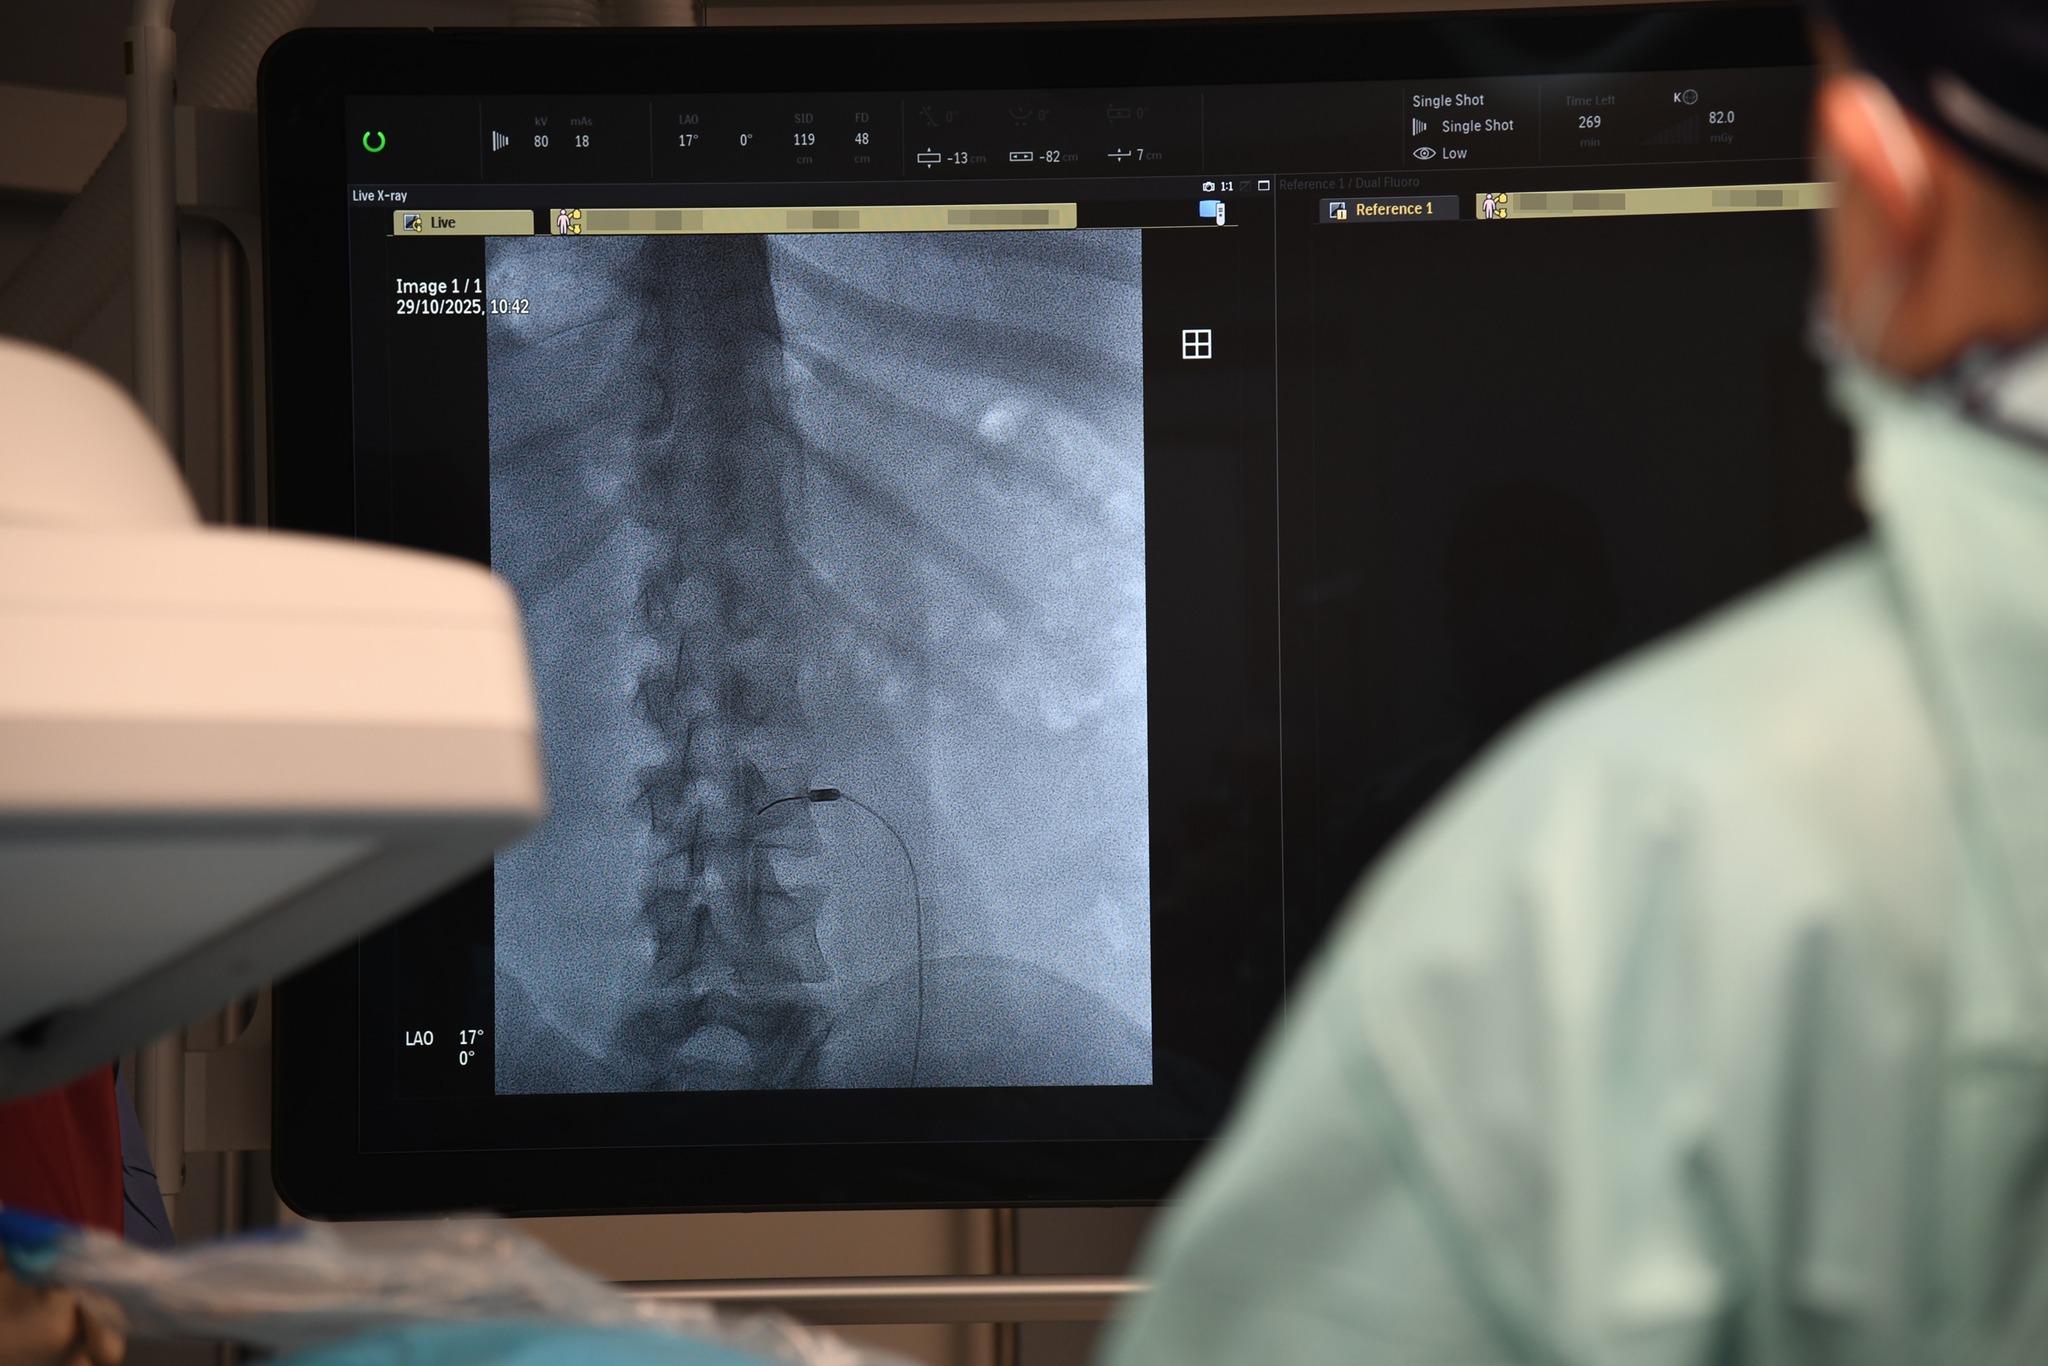

- Przykładowo mamy pacjenta z bólem, zwanym, rzekomo-korzeniowym - mówi Rafał Muchowski, neurochirurg z Oddziału Neurochirurgii Wojewódzkiego Szpitala Specjalistycznego w Słupsku. - Nie ma dyskopatii, natomiast bardzo go bolą plecy. Z czego może wynikać ten ból? Z przeciążenia stawów międzykręgowych. Co możemy wtedy zrobić? Zniszczyć unerwienie tych stawów. Robimy to wbijając igłę, pod kontrolą prześwietlenia rentgenowskiego, bo jest to metoda wymagająca precyzji. Do igły wprowadzamy emiter prądów wysokiej częstotliwości i nagrzewamy tkanki do temperatury – w tym konkretnym przypadku – 85 stopni Celsjusza. Nagrzewamy miejscowo tylko tę strukturę, która nas interesuje, bo pole rażenia tej elektrody jest niewielkie

Wysoki poziom wykonywania termolezji w słupskim szpitalu jest możliwy dzięki używanemu sprzętowi wysokiej klasy, np. nowoczesnemu angiografowi zakupionemu przez szpital na początku 2025 r. Termolezja stosowana może być głównie u osób, które nie mogą być poddawane farmakoterapii lub mają niewydolną wątrobę lub mają niesprawne nerki. Duże nadzieje związane są ze zastosowaniem termolezji u chorych onkologicznie. Termolezje można wykonywać także u chorych onkologicznie z silnymi dolegliwościami bólowymi, np. w obrębie brzucha.